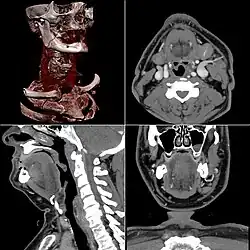

Head & Neck Imaging

CT scan remains the cornerstone imaging modality for the initial evaluation and subsequent management of patients with acute traumatic brain injury due to its rapid acquisition time and high sensitivity for detecting hemorrhagic complications, such as intraparenchymal hematomas and subdural hemorrhages.[56] CT scan of the head is typically used to detect infarction (stroke), tumors, calcifications, haemorrhage.[57] Tumors can be detected by the swelling and anatomical distortion they cause, or by surrounding edema. CT scanning of the head is also used in CT-guided stereotactic surgery and radiosurgery for treatment of intracranial tumors, arteriovenous malformations, and other surgically treatable conditions using a device known as the N-localizer.[58][59][60][61][62][63]

Contrast CT is generally the initial study of choice for neck masses in adults.[64] CT of the thyroid plays an important role in the evaluation of thyroid cancer.[65] CT scan often incidentally finds thyroid abnormalities, and so is often the preferred investigation modality for thyroid abnormalities.[65]